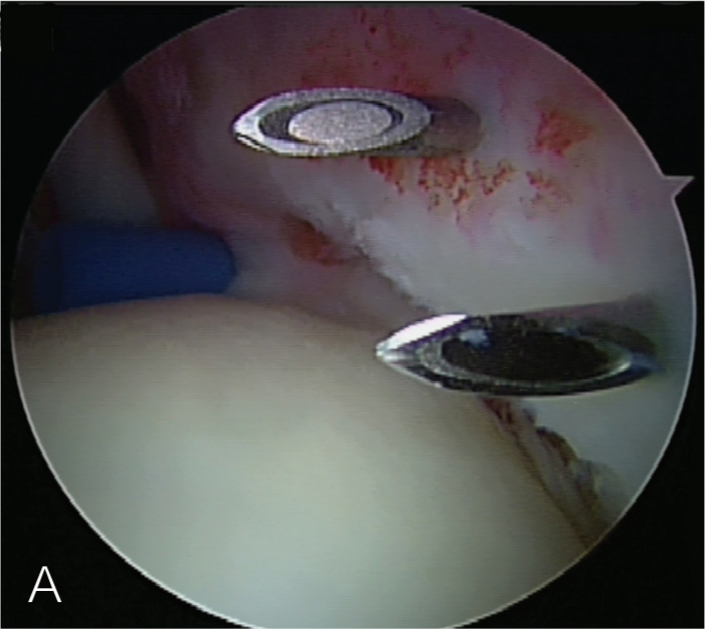

创建前方和后方入路时,与关节盂面成恰当角度,以便锚钉的置入。 高位和外侧放置前方入路可以有效地进行单纯上盂唇的修复。该入路位于肩袖间隙的高位和外侧,用腰椎穿刺针进行定位。非刚性套管有助于在肱二头肌腱附着部后方置入锚钉。 可用于 SLAP 修复的辅助入路包括 Wilmington 入路(肩峰后外侧角前方、外侧各 1 cm 处)或 Neviaser 入路(锁骨、肩峰、肩胛冈组成的三角形内,肩峰内侧 1 cm 处)。

B. 应首先用腰椎穿刺针确定辅助入路的恰当位置和方向。然后在皮肤上做一个小切 A B 口,钻头导向器置入关节。

修复处准备